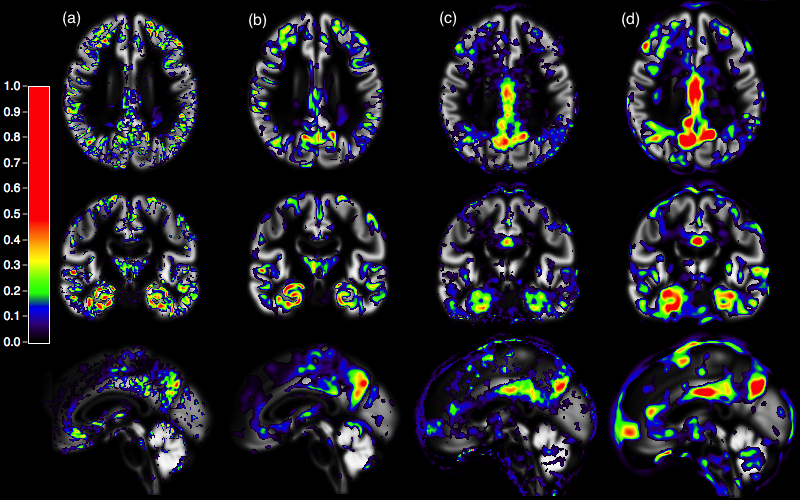

Refer to caption

Figure 1: Normalized woptsuperscript𝑤𝑜𝑝𝑡\displaystyle w^{opt} coefficients \displaystyle\geq 0 for AD vs CN: (a) T1 linear SVM,                         (b) T1 regularized SVM, (c) FDG PET linear SVM, (d) FDG PET regularized SVM